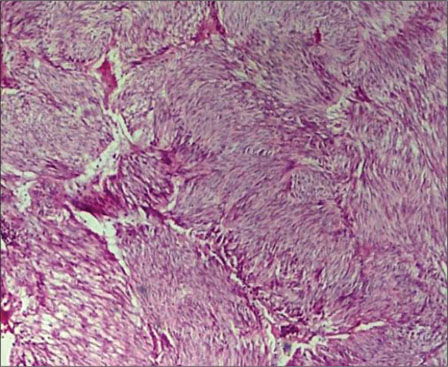

A total of 90 mesenchymal tumors of the GIT and pancreas diagnosed in SKIMS from January 2010 to December 2016 were reclassified on the basis of morphologic features and IHC into 77 (85.6%) cases of GIST and the remaining 13 (14.4%) cases as other mesenchymal tumors. The mesenchymal tumors included five cases of inflammatory myofibroblastic tumors, two cases of leiomyoma, four cases were sarcomas, one case was poorly differentiated carcinoma, and one was desmoid tumor. C-KIT positivity was seen in 72 (93.5%) cases and DOG 1 was positive in 77 (100%) cases [Figures 1], [2], [3], [4]. However, the correlation between DOG1 and CKIT was found to be statistically insignificant (P = 0.23). There was no significant association between DOG 1 expression and various histopathological parameters in the studied cases. Clinicopathological variables have been enumerated in [Table 1].

| Figure 2 Microscopic view of gastrointestinal stromal tumor

|